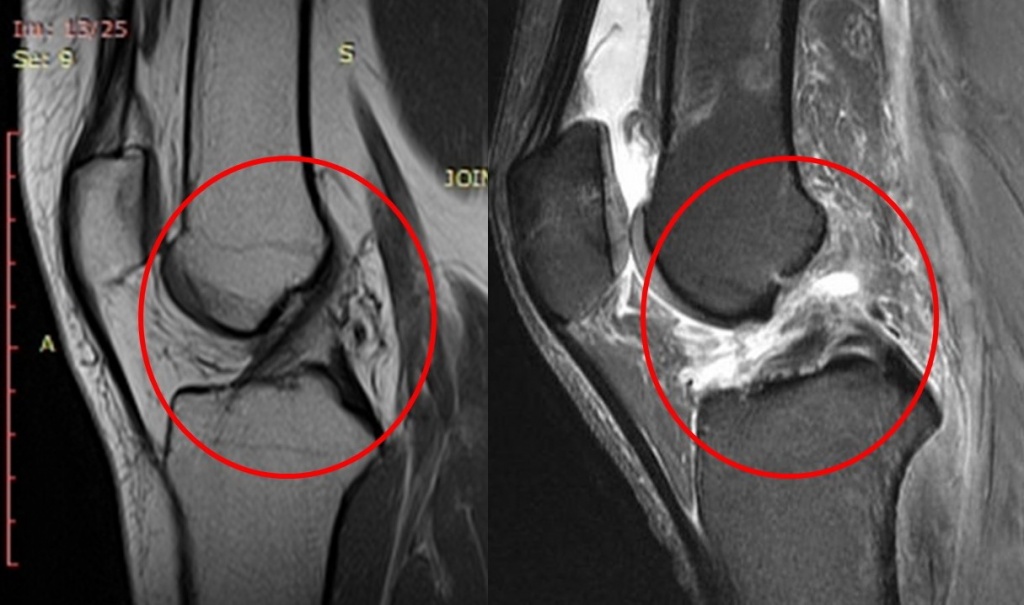

Диагноз ставится после тщательного обследования. Врач-травматолог проводит опрос, просит детально описать механизм получения травмы, затем выполняет осмотр с проведением клинических тестов. Для подтверждения диагноза и исключения других повреждений обязательно выполняют магнитно-резонансную томографию.